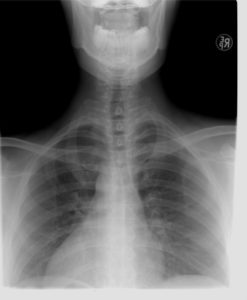

Røntgenundersøgelse